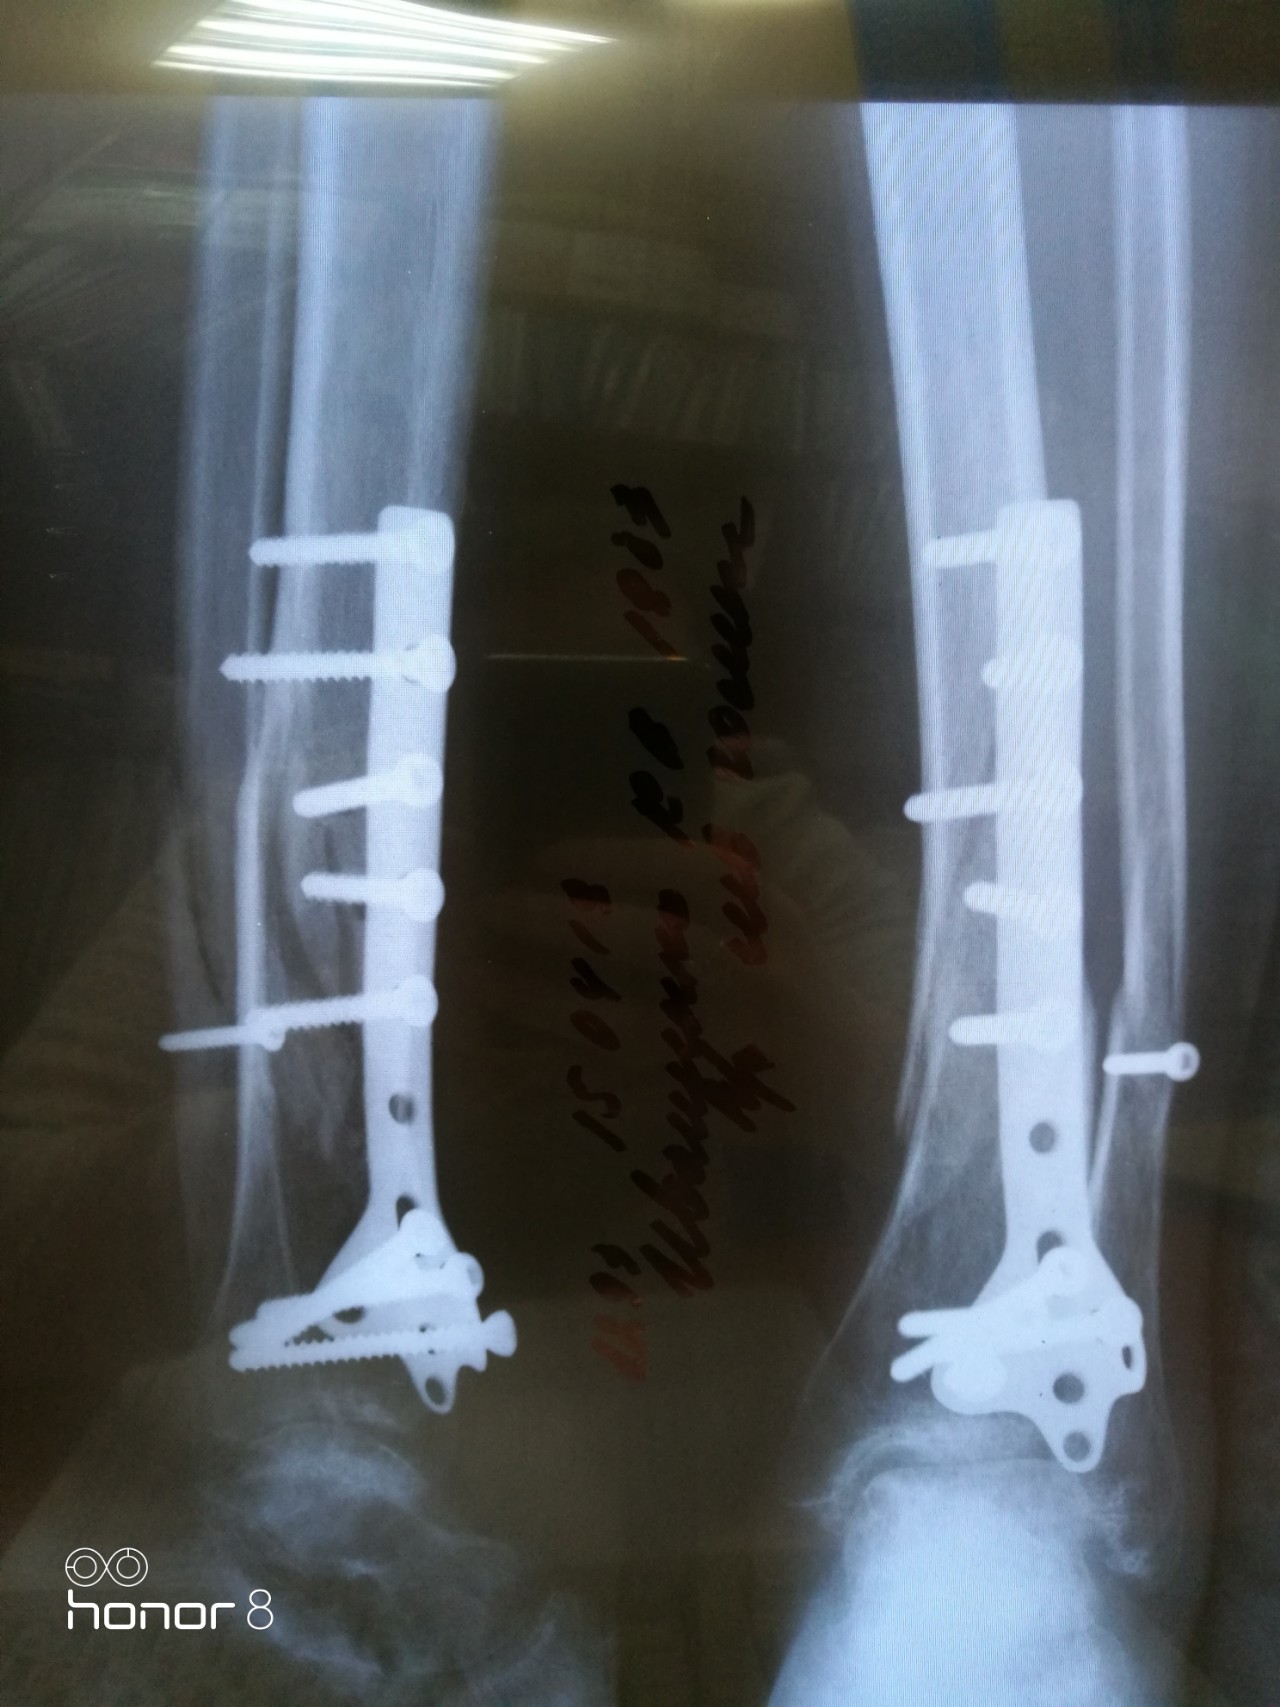

Перелом большой берцовой кости - серьезное повреждение, сопровождающееся болезненными ощущениями и нарушением функции ноги. На этой странице вы найдете много фотографий, позволяющих вам более детально изучить эту травму.

Чрескостный остеосинтез лодыжки

Остеосинтез двухлодыжечного перелома

Здесь представлены медицинские изображения переломов большой берцовой кости, сделанные врачами в процессе диагностики и лечения. Вы сможете увидеть, как выглядит этот тип травмы на рентгеновских снимках и других медицинских изображениях.